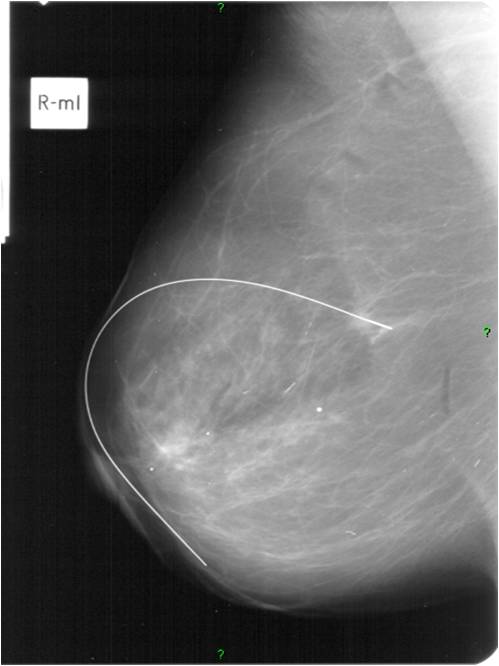

2. Digital mammography has displaced the analogue technic for today almost everywhere: (pictures 1,2,3) phosphorous plate or direct digital methods. For breast imaging the latter is the method of choice. Phases of image production separate. The image is produced on the detectors, but appears on the high resolution monitor and can be stored as a digital data set at various storage mediums (e.g.: CD, hard disk drives).

Image

Picture 1.

Picture 2.

Picture 3.